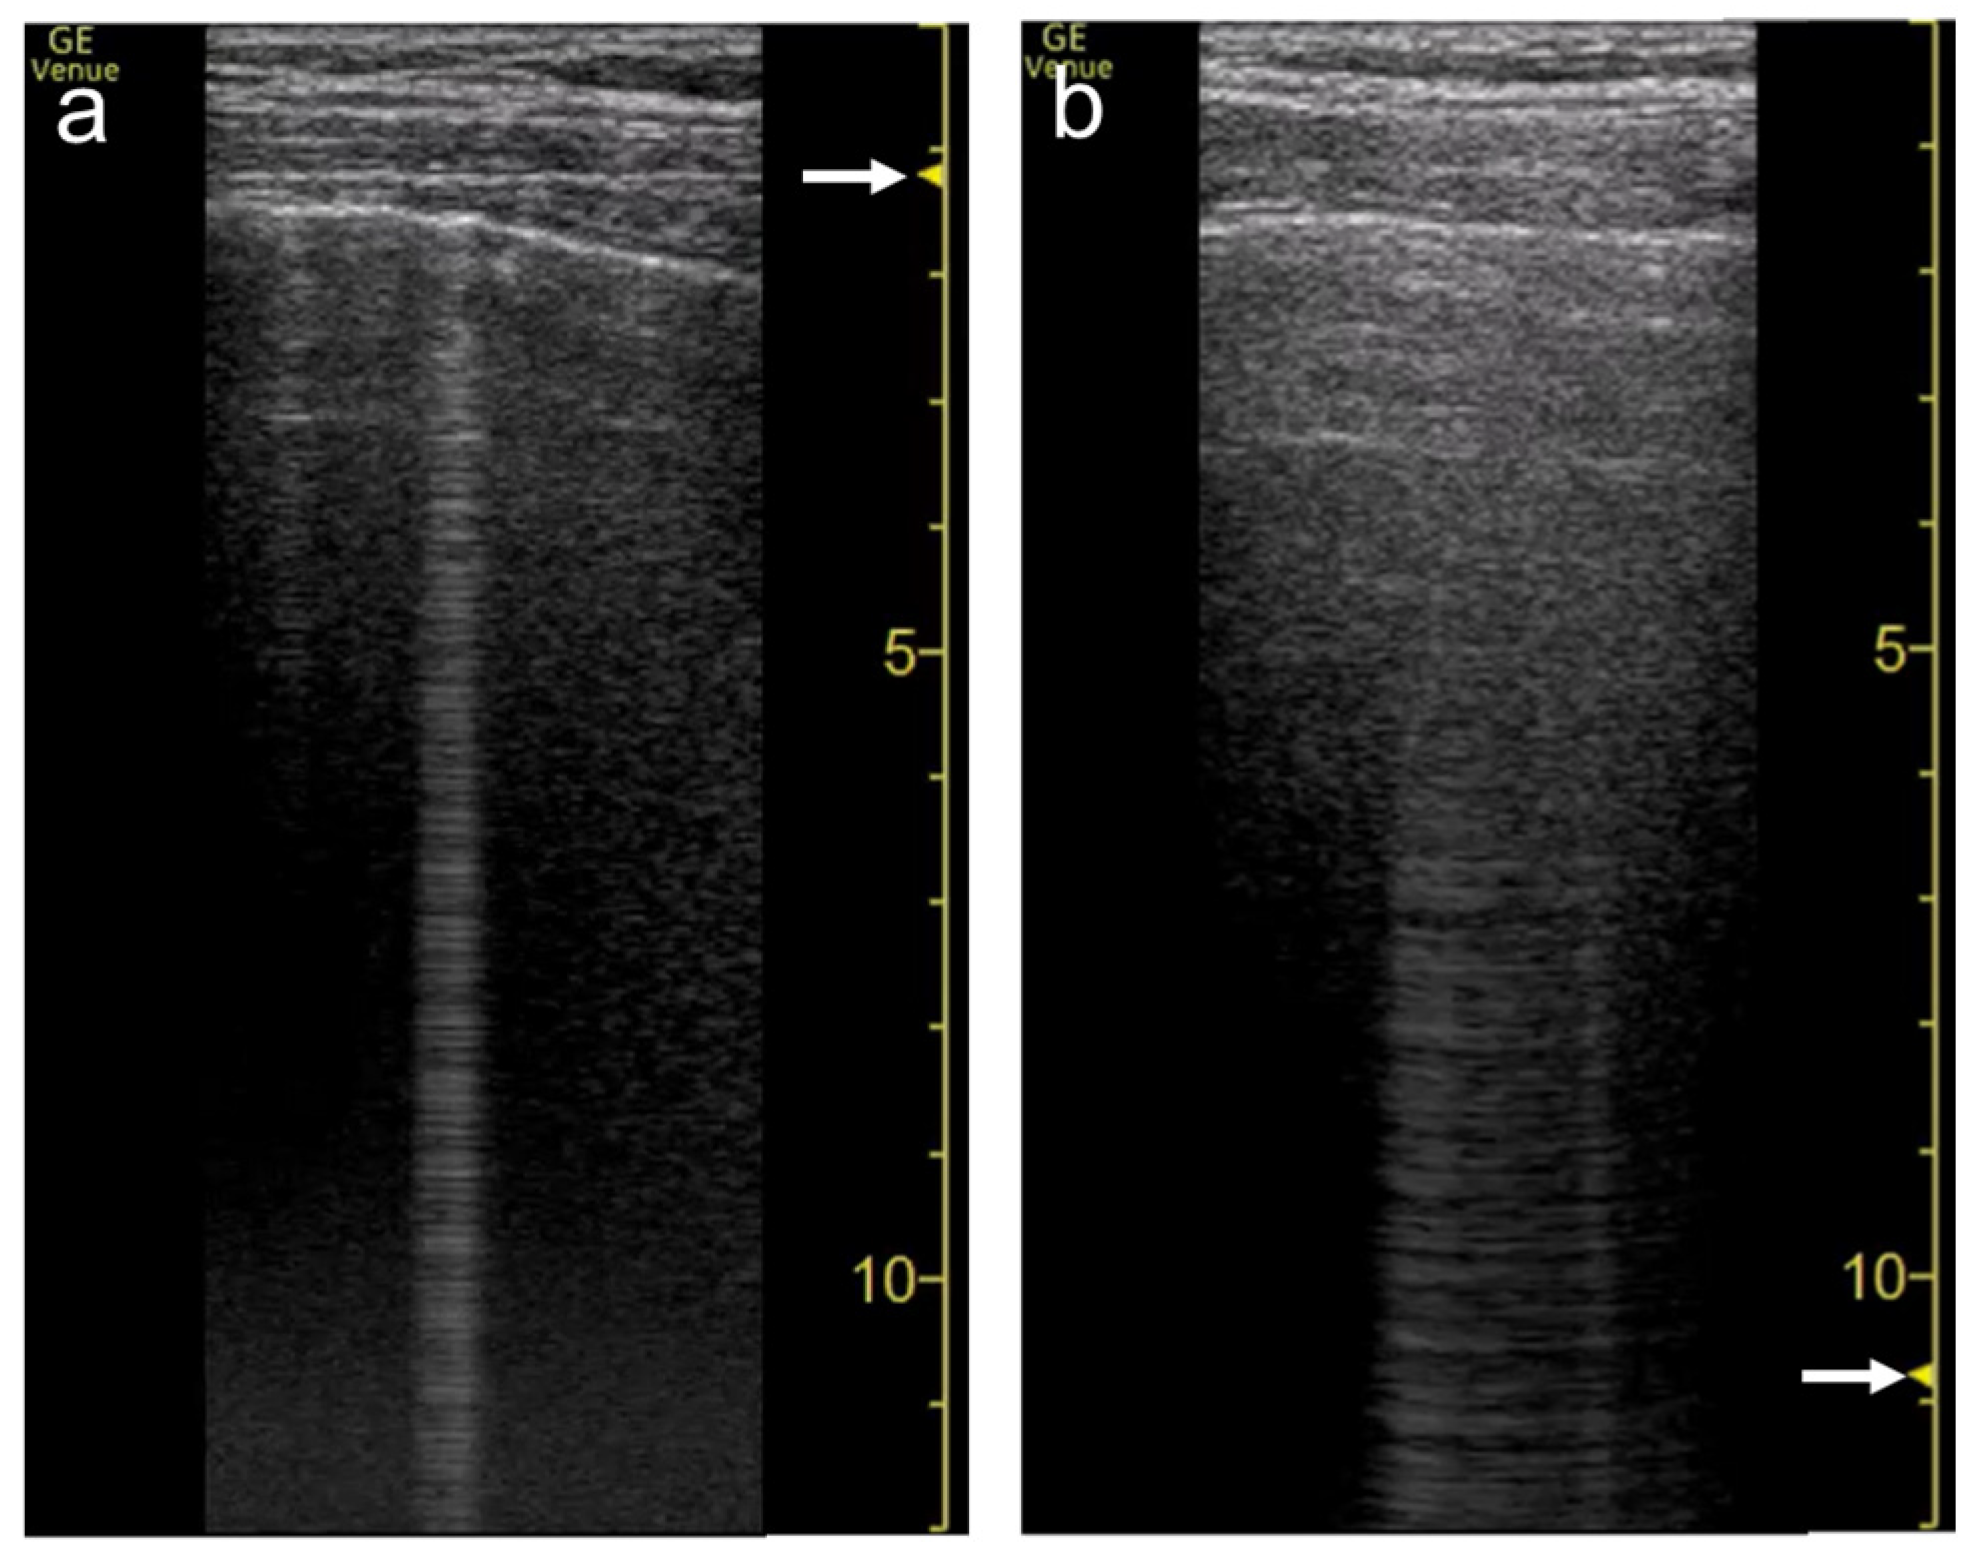

3.1. Spatial Compound Imaging

3.3. Frequency